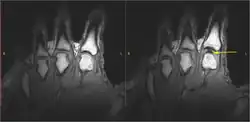

Diese Theorie wurde in einem 2015 veröffentlichten wissenschaftlichen Artikel unter anderem von Gregory N. Kawchuk bestätigt. Zugleich wurde eine Theorie aus dem Jahre 1971, welcher zufolge das Knacken durch das Zerplatzen der Blasen entsteht, widerlegt.[2][3]